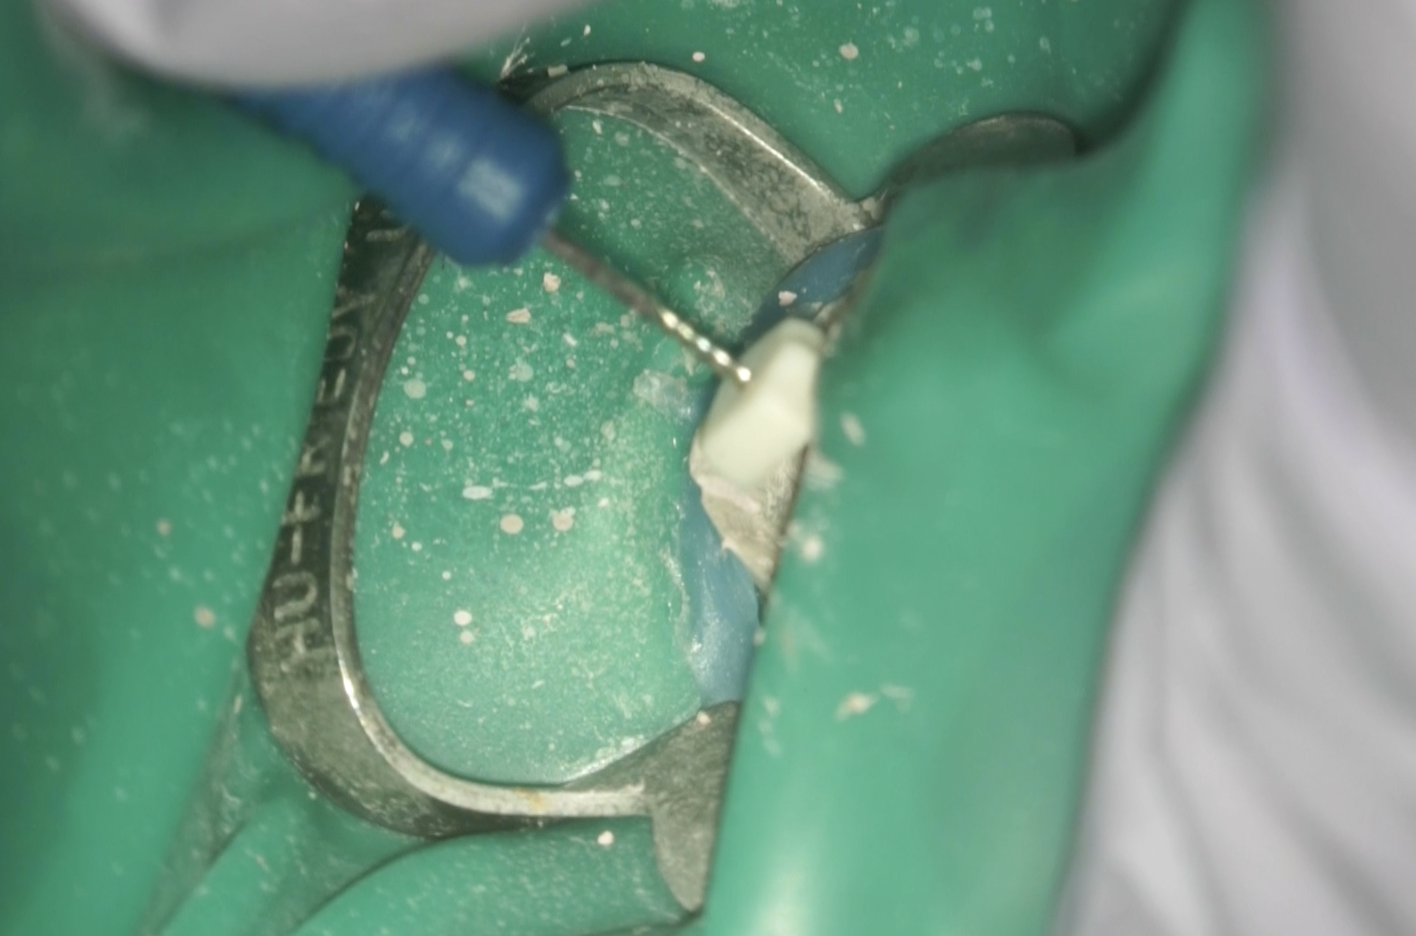

#30 Re-RCT(2025.10.21)

再治療ではGutta Percha Point除去に頭を悩ませる人が多いが、私はC-solutionをUSC時代から使用するのであまり苦になったことがない。

C-solutionを窩洞内に浸し超音波でホールをつけて引っ掛けると簡単に除去できた。